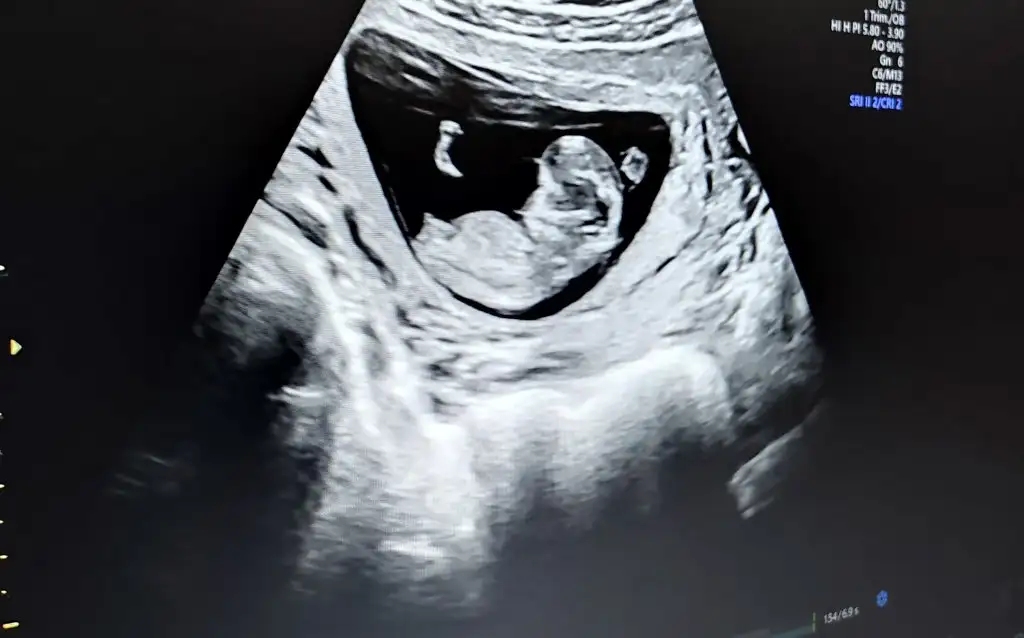

14+3 tahminde bulunurmusunuz🤦‍♂️

• USER_SCOPED_TEMP_DATA_MSGR_PHOTO_FOR_UPLOAD_1619699207153_6793510863365994738.webp

USER_SCOPED_TEMP_DATA_MSGR_PHOTO_FOR_UPLOAD_1619699207153_6793510863365994738.webp

24,1 KB · Görüntüleme: 67